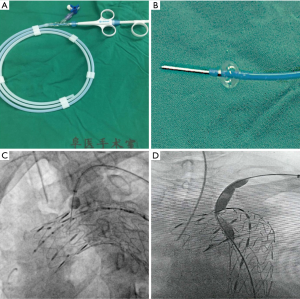

In-situ needle fenestration procedure

First, the aortic stent-graft was introduced to the aortic arch and deployed at the planned landing zone. Then, a balloon expandable puncture needle (Lifetech, Scientific Co., Ltd, Shenzhen, China; Figure 4A,B) was introduced through the Fustar steerable vascular sheath (Lifetech) from the brachial access and advanced to the orifice of the LSA. The fenestration was created by inflating the balloon to activate the puncture needle (Figure 4C). Then, the guidewire was passed through the newly created fenestration to reach the aortic lumen. After balloon expansion of the fenestration site (Figure 4D), a covered stent-graft was deployed to ensure patency of the aortic branch. Finally, the stent-graft for the aortic branch was again dilated via a balloon, and completion DSA was performed to check the result.